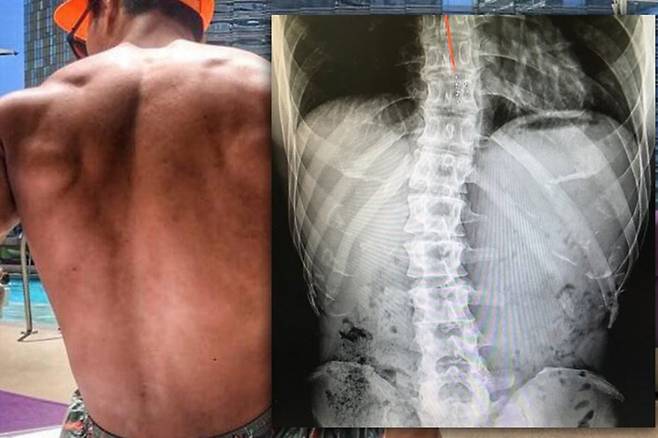

결국 2016년, 김종국은 자신의 SNS에 척추 사진을 업로드합니다. 공개한 엑스레이 사진 속 김종국의 척추는 누가 봐도 심각하게 휘어져 있었죠. 김종국은 "고등학교 때 허리 통증으로 쓰러졌다"라며 휘어진 척추를 잡아주기 위해 근육을 만들어야 했다고 밝혔습니다.

또 사진을 올려도 믿지 않을 사람이 있을 것이라며 "좀 하나라도 느껴보자들. 딱해서 그래"라며 그간 논란에 한을 쏟아냈습니다.